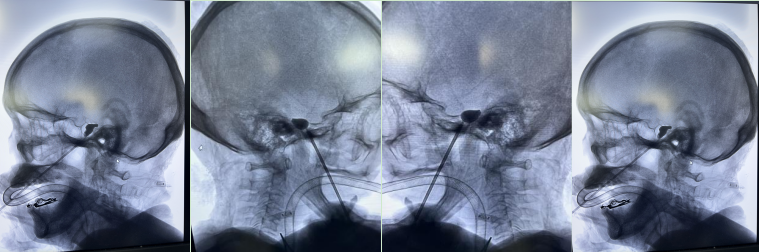

术中影像图

9月19日晚上,神经外科在麻醉科、介入科的协助下,先后为陈婆婆和张爷爷顺利完成了手术,整个手术操作过程约30分钟,术后患者口角外侧仅一个小小的针眼,且清醒后右侧额面部疼痛完全消失,当天就能正常进食,下地行走,治疗效果十分显著。